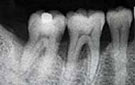

歯周病の治療方針

歯周病はバイオフィルムという歯周病菌の塊が歯根にへばりつき毒素をばらまき、歯を支える骨を知らないうちに溶かす怖い病気です。キッチンの流しで食器を毎日洗っていると排水溝にヌメリが付きます。しっかりスポンジで洗い流してツルツルしてもしばらくするとまた汚れます。同じようなことが私たちのお口の中でも起こっています。毎日歯を磨いていても歯ブラシの届かない歯茎の中は歯周病菌が集まって棲みつくのです。

歯周病は毎日の歯磨きの習慣と咬みあわせの調整でほとんど解決します。